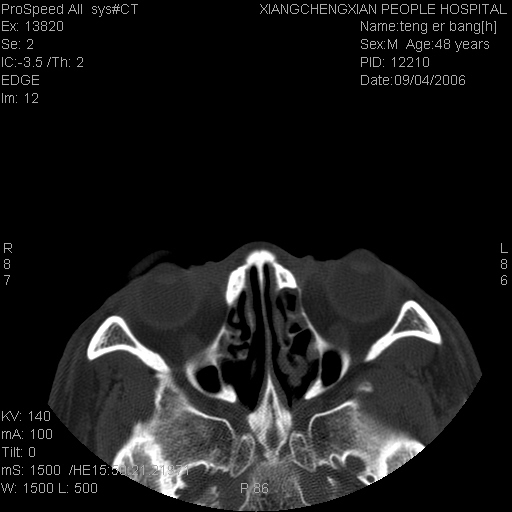

ct:平扫+冠扫:双侧鼻骨对比,冠扫s6#示右侧鼻骨尖部可见线状低密度影,边缘光滑,并见硬化.软组织未见肿胀.

诊断意见:鼻额缝(鼻骨与上颌骨额突缝),但个别同志认为是骨折.因此请同行们会诊.多谢了!